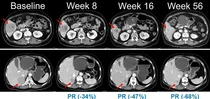

〈사진〉 NRAS 돌연변이 흑색종 환자를 대상으로 진행된 벨바라페닙과 코비메티닙 병용요법 임상시험에서 시간 경과에 따른 병변 변화가 관찰된 복부 CT 영상.

국내외 치료제 없는 NRAS 돌연변이 흑색종 유의미한 효능박재현 대표 “적절한 치료 수단 없어 고통받는 암 환자들에희망 줄 수 있는 혁신적 신약 개발 흔들림 없이 매진" 밝혀▲NRAS 돌연변이 흑색종 환자를...